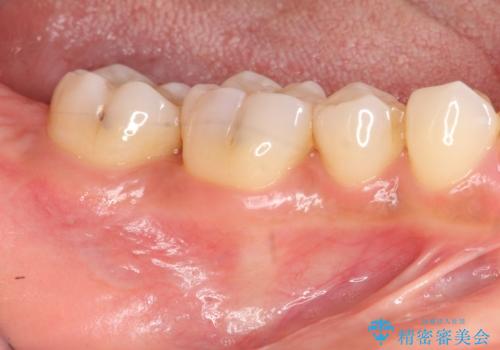

再生治療を行うことで、吸収した骨を再生し歯を保存できることがあります。

- 歯周組織再生治療は患者様の状態によって術後の経過が異なります(見た目が改善しない場合もあります)